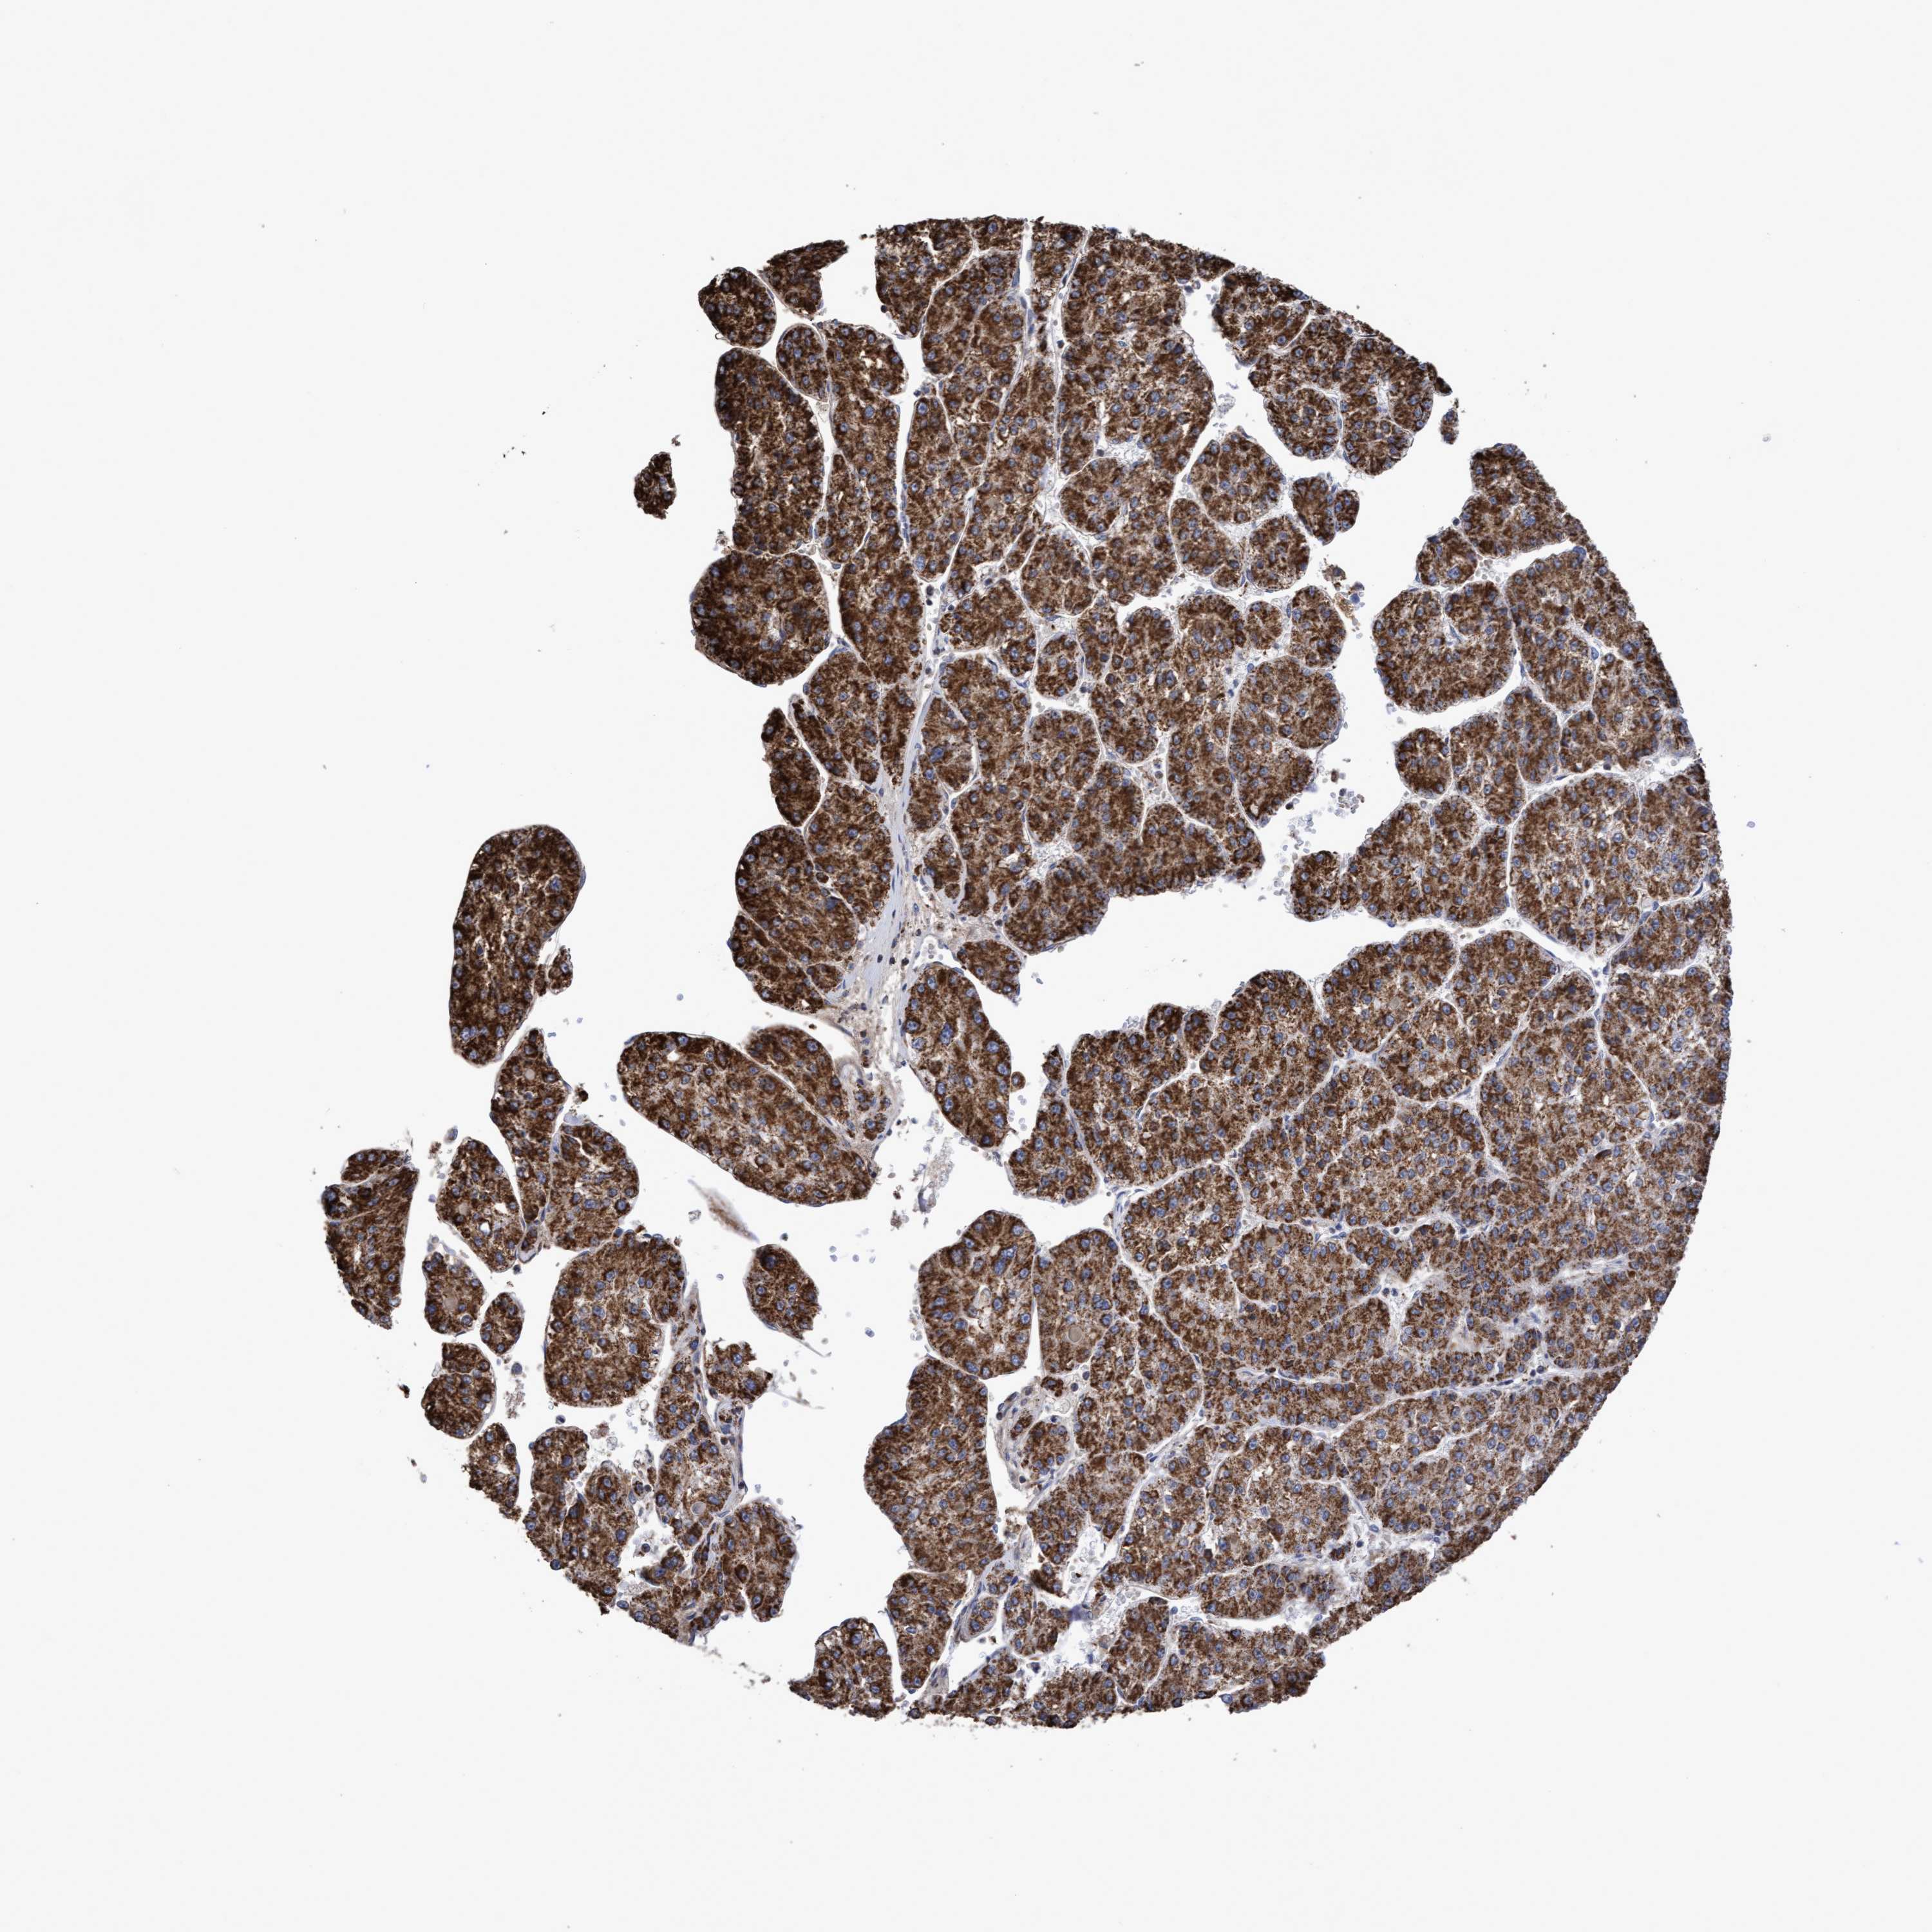

LIVER CANCER - Protein expressioni

A mouse-over function shows sample information and annotation data. Click on an image to view it in a full screen mode. Samples can be filtered based on level of antibody staining by selecting one or several of the following categories: high, medium, low and not detected. The assay and annotation is described here.

Antibody stainingi

Antibody staining in the annotated cell types in the current human tissue is reported as not detected, low, medium, or high, based on conventional immunohistochemistry profiling in selected tissues. This score is based on the combination of the staining intensity and fraction of stained cells.

Each image is clickable and will lead to virtual microscopy that enables deeper exploration of all samples and also displays staining intensity scores, fraction scores and subcellular localization as well as patient and tissue information for each sample.

Antibody HPA019033

Antibody HPA019167

Staining

High

Medium

Low

Not detected

Intensity

Strong

Moderate

Weak

Negative

Quantity

>75%

75%-25%

<25%

None

Location

Nuclear

Cytoplasmic/membranous

Cytoplasmic/membranous,nuclear

Cholangiocarcinoma

Carcinoma, Hepatocellular, NOS